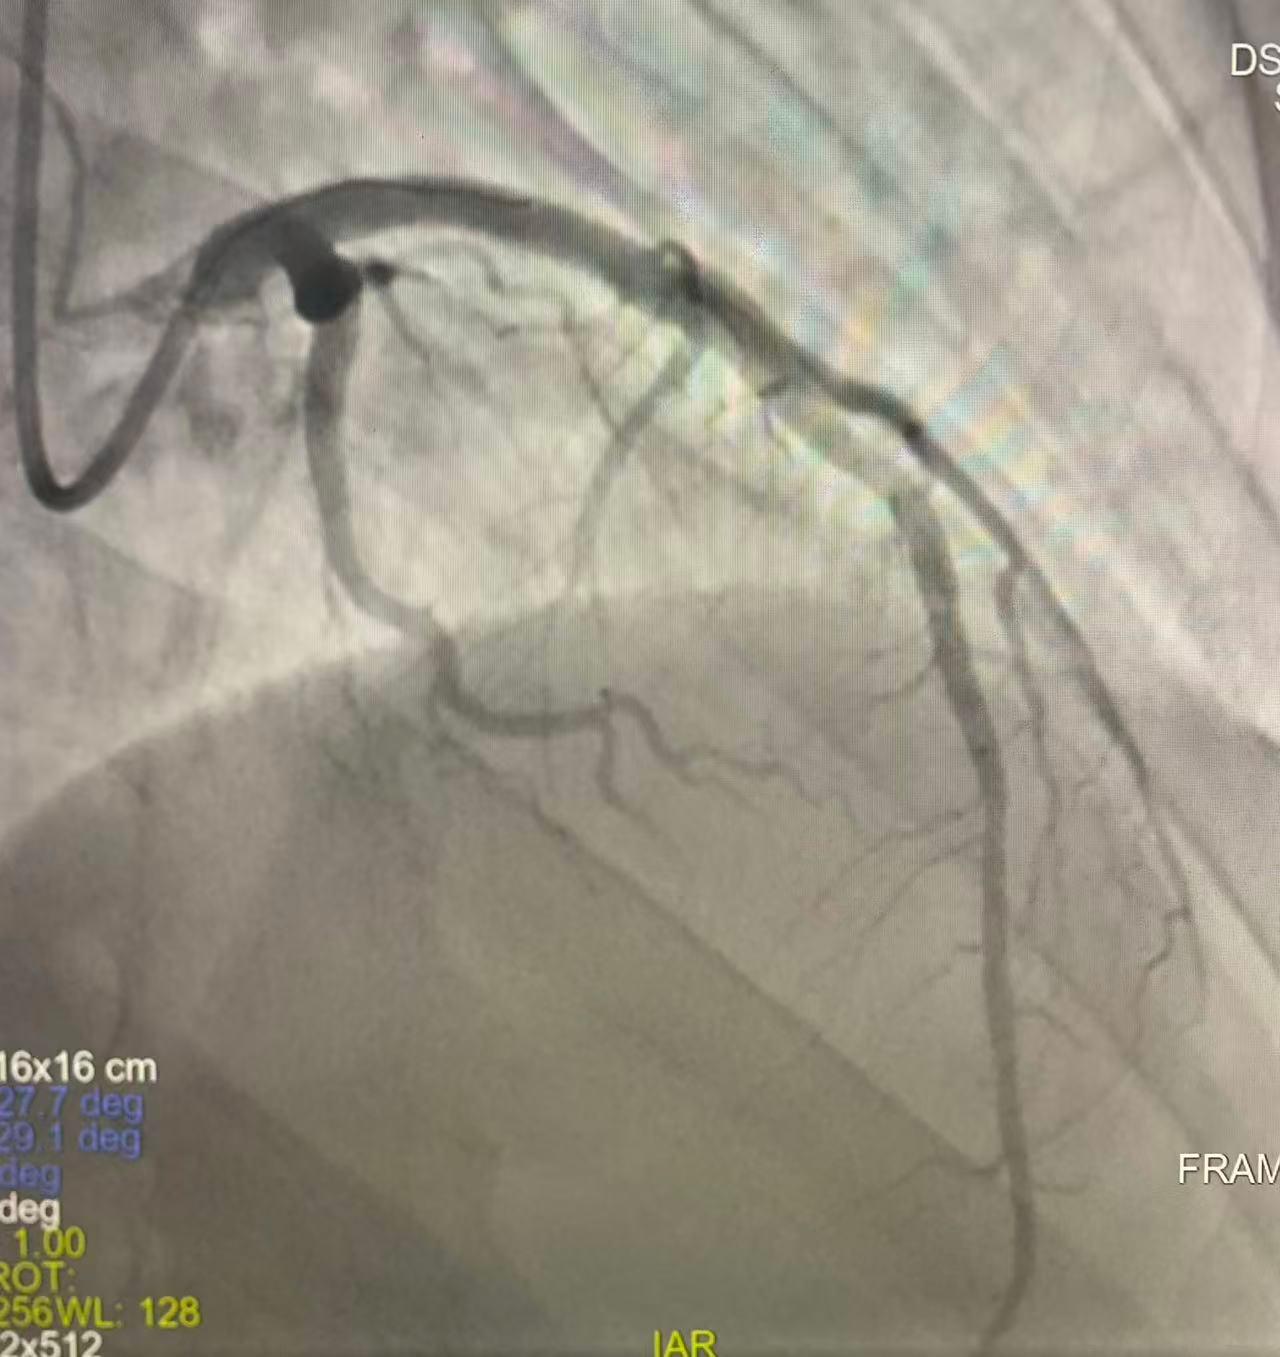

术后

就在刚转运至介入手术室时,患者突发室颤,心血管病院副院长刘云凤立即指导抢救,马玉娥医生行胸外按压、介入手术室紧急电除颤,转复窦律……经医护人员全力抢救,患者意识逐渐转清,在介入室行急诊PCI,冠脉造影提示左前降支LAD近段几乎全闭塞,顺利植入一枚支架,开通闭塞冠脉血管,实现梗死冠脉血流灌注。